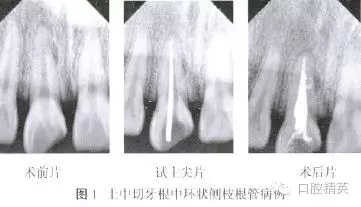

患者,男,24歲,因右上頜中切牙破損、變色10余年,近1個月反復(fù)出現(xiàn)牙齦腫脹、瘺管,咬合疼痛等癥狀。于2013年7月就診。檢查:右上中切牙牙冠色暗,切端近中斜折,髓腔暴露,內(nèi)有少量腐質(zhì),叩痛(+),無松動,頰側(cè)牙齦距離齦緣3 mm處可見瘺管。瘺管處牙齦腫脹約2 mm×2 mm。X線片示根管內(nèi)無充填物,根中近中側(cè)可見弧形低密度影像,根尖周圍低密度影像(圖1)。

紙尖干燥根管,2%葡萄糖酸洗必泰溶液浸泡根管1 min。紙尖干燥根管,使用螺旋充填器將氫氧化鈣糊劑導(dǎo)入根管內(nèi),氧化鋅嚴(yán)密封填?;颊?周后復(fù)診,牙齦瘺管及腫脹消失,患牙無叩痛,去除暫封物,3%次氯酸鈉溶液沖洗根管,去除氫氧化鈣。將牙膠尖35.~04使用GP Size Creator修剪至50.~04后試主尖,拍攝X線片示主尖尖端距離根尖約1 mm(圖1)。紙尖干燥根管,試熱壓尖F.一06、Buchanan垂直加壓器及23G熱牙膠回填膠囊針頭。紙尖干燥根管,3%次氯酸鈉溶液浸泡根管,I耐一Safe超聲蕩洗尖距工作長度l mm連續(xù)蕩洗根管2次,每次20 s。

拍攝X線片根中遠(yuǎn)中側(cè)可見兩個側(cè)枝根管充填后形成的環(huán)形影像(圖1)。氧化鋅嚴(yán)密封填,擬觀察2周后行樁核冠修復(fù)。以上所有治療均得到患者知情同意。